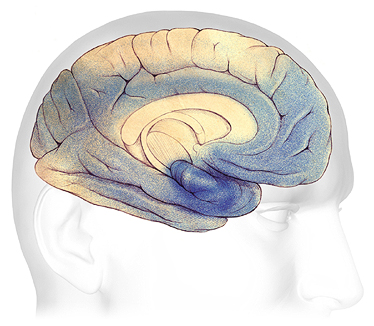

Au stade sévère de la maladie d’Alzheimer, la majeure partie du cortex est sérieusement endommagée. Le cerveau rétrécit de façon spectaculaire à la suite de la mort généralisée des cellules. Les individus perdent leur capacité à communiquer, à reconnaître leurs proches et amis et à s’occuper d’eux-mêmes.